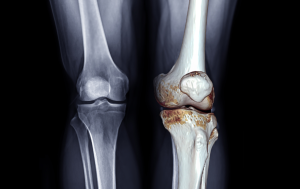

What is Knee Osteoarthritis?

Osteoarthritis is a common type of arthritis that affects millions of people. It occurs when the protective cartilage that cushions the ends of your bones wears down over time. This can cause the bones to rub against each other, leading to a host of unpleasant symptoms. Because your knees are a major weight-bearing joint, they are particularly susceptible to this condition.

Osteoarthritis (OA) is a common degenerative joint disease that primarily affects the smooth tissue that covers the ends of bones in a joint, known as cartilage. While osteoarthritis can occur in any joint, it most frequently impacts the knees, hips, hands, and spine.